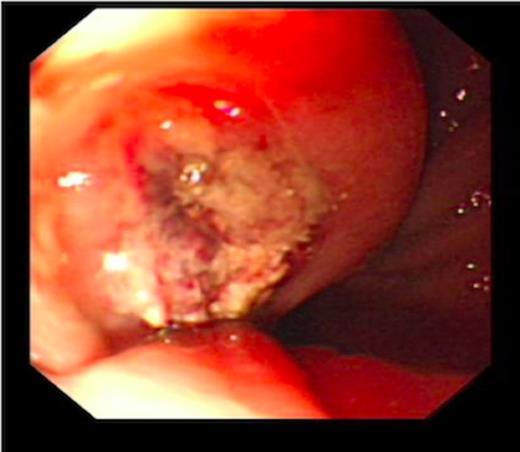

An endoscopy performed four years post-operatively demonstrated two atypical acute gastric ulcers in the distal stomach (figure 1), which were treated with a heat probe (figure 2). Two days later she presented as an emergency in hypovolaemic shock following a large volume haematemesis (haemoglobin of 40g/l). An urgent upper gastrointestinal endoscopy revealed a visible vessel at 35 cm forming part of an expansive mass within the gastric conduit. EUS demonstrated a heterogeneous mass indenting the gastric conduit, containing a strong Doppler signal (figure 3). An urgent computerised tomography (CT) angiogram revealed a Type-A thoracic aortic aneurysm with an enteric fistula (figure 4). The saccular aneurysm of the thoracic aorta was embedded in the gastric conduit. A 28x16cm Valiant® (Medtronic Ltd, Minneapolis, USA) stent was placed in the descending thoracic aorta with good occlusion of the aneurysm. The patient made an excellent recovery and was discharged on the seventh day post stenting.